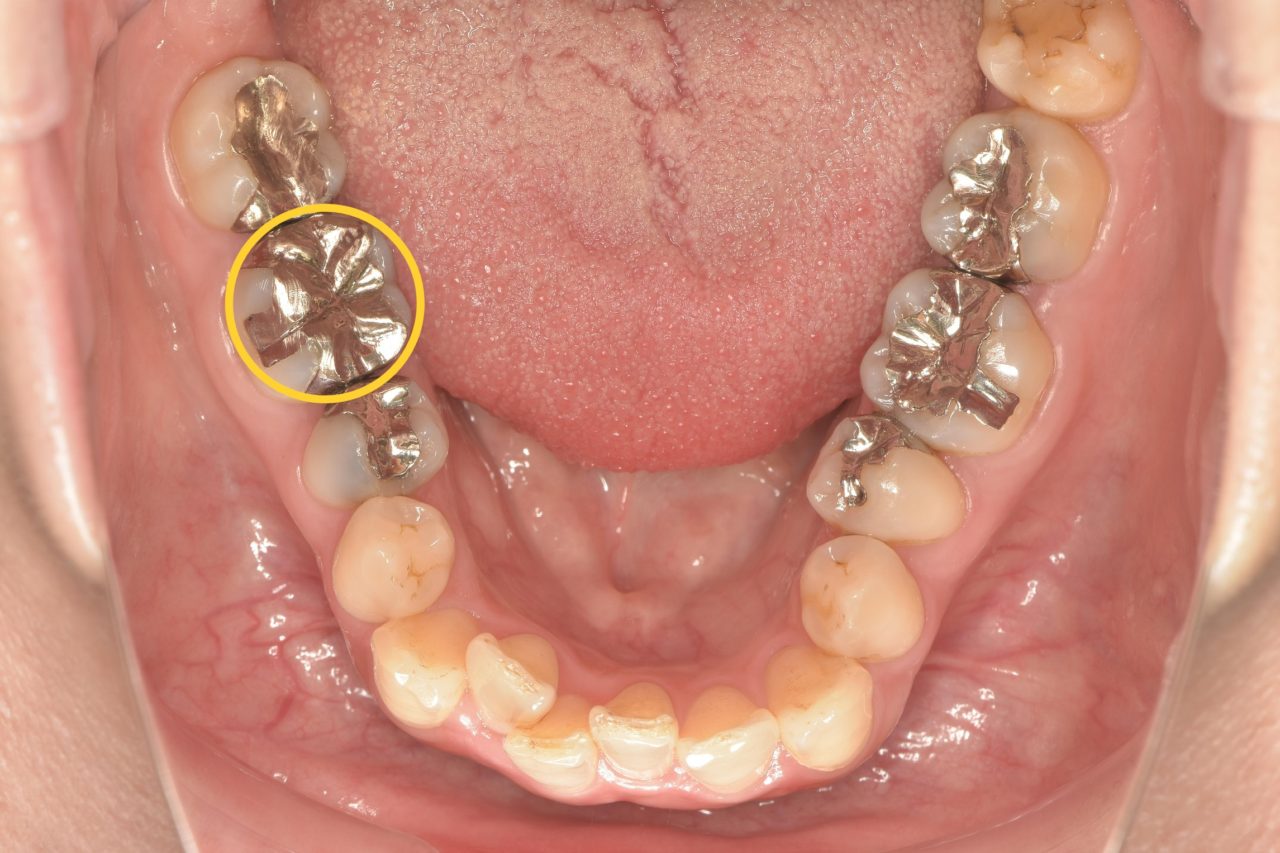

初診時の口腔内写真です。他院での根管治療の際にリーマーが折れ、歯の中に残ってしまっている症例です。

リーマーとは根管治療の時に使う器具のことです。

リーマーは治療中に折れてしまうことがあり、折れたことに気付かないまま、あるいは説明をせずに治療を終えてしまう歯科医院もあります。

その為、後から折れた器具が歯の中から見つかり、残念ながら患者様に説明がなされていないケースも見受けられます。 -

レントゲン写真をご覧ください。この直線的に写っている怪しい影が破折リーマーです。